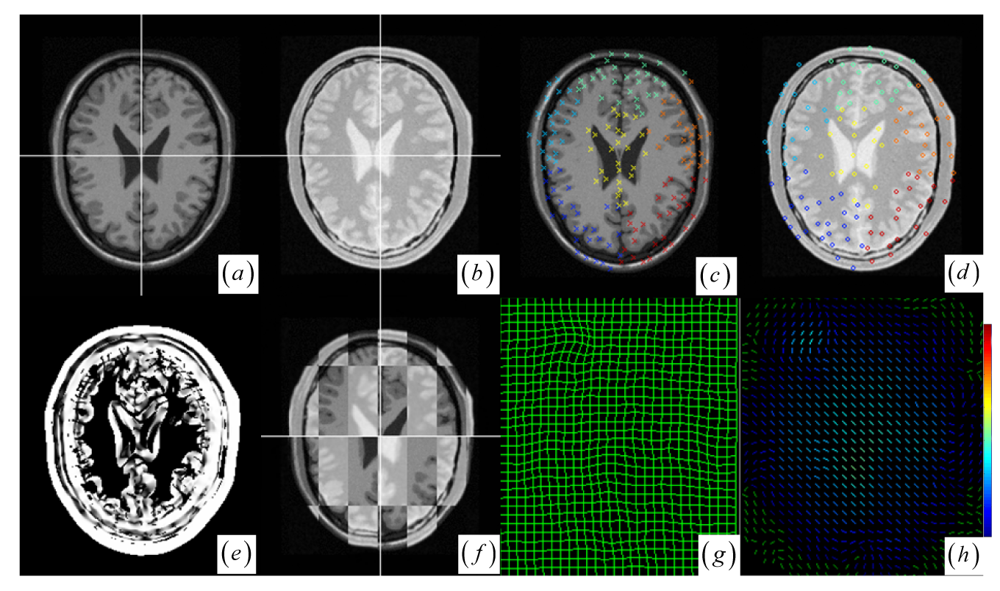

A JSM value near one suggests that the underlying pixel pair comes from the corresponding spatial structures. Contrarily, a JSM value near zero indicates that the pixel pair originates from either the outliers or a homogeneous region. To speed up the rigid registration procedure without reducing accuracy, the registration only uses the salient pixel pairs with large saliency values. The pixel with a small saliency value below a fixed threshold value (10 percent of the maximum saliency value) is assigned zero JSM value directly. Generally, the JSM would primarily respond to the high-gradient common edges in both images if a high threshold is chosen to exclude more pixels from estimating the JSM. However, as in the Figure 1c–e representing the image gradient and the JSM profiles of the same line at the two registered images (see Figure 1a,b), the JSM (see Figure 1e) consistently captures the corresponding regional salient structures in the two images while the image gradient features (see Figure 1c,d) are very noisy and do not agree with each other at each overlapping location.

Figure 1. (a)–(b) Intra- and pre-operative MR images with tumor resection. (c)–(d) Gradient value profiles of the lines in (a)–(b), which are marked as dashed lines. (e) JSM value profiles of the lines in (a)–(b). (f) Joint histogram dispersion with two clotted clusters (dark red in pseudo color). (g) The JSM-weighted joint histogram with smoothed compact clusters for (a)–(b). (h) JSM for the two images in (a)–(b) with low JSM values at the tumor resection area. (i) The intra-operative MR image and the circle marked DoG keypoints. (j) The pre-operative image and resultant keypoint clustering with circle marked floating keypoints and cross marked reference keypoints. Different colors mean different clusters.